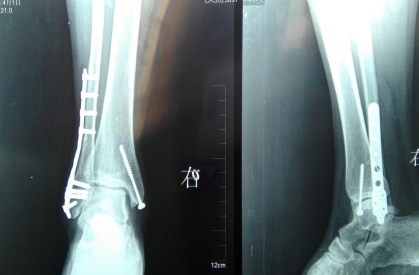

内外踝骨折